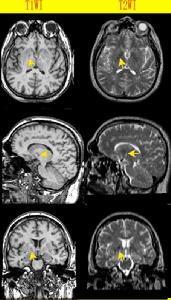

根據青少年期出現進行性錐體外系症狀肌張力障礙肌強直和雙下肢痙攣性癱等MRI檢查T2WI顯示典型“虎眼征”,可以診斷本病,陽性家族、骨髓巨噬細胞中或周圍血淋巴細胞中分辨到海藍色組織細胞或59Fe標記的鐵鹽的SPECT顯像在雙側基底核區有放射性聚積及消失緩慢,則可證實本病

蒼白球黑質紅核色素變性2.MRI檢查T2WI示雙蒼白球外側低信號內側有小的高信號稱為“虎眼征”(eyeofthetiger)。